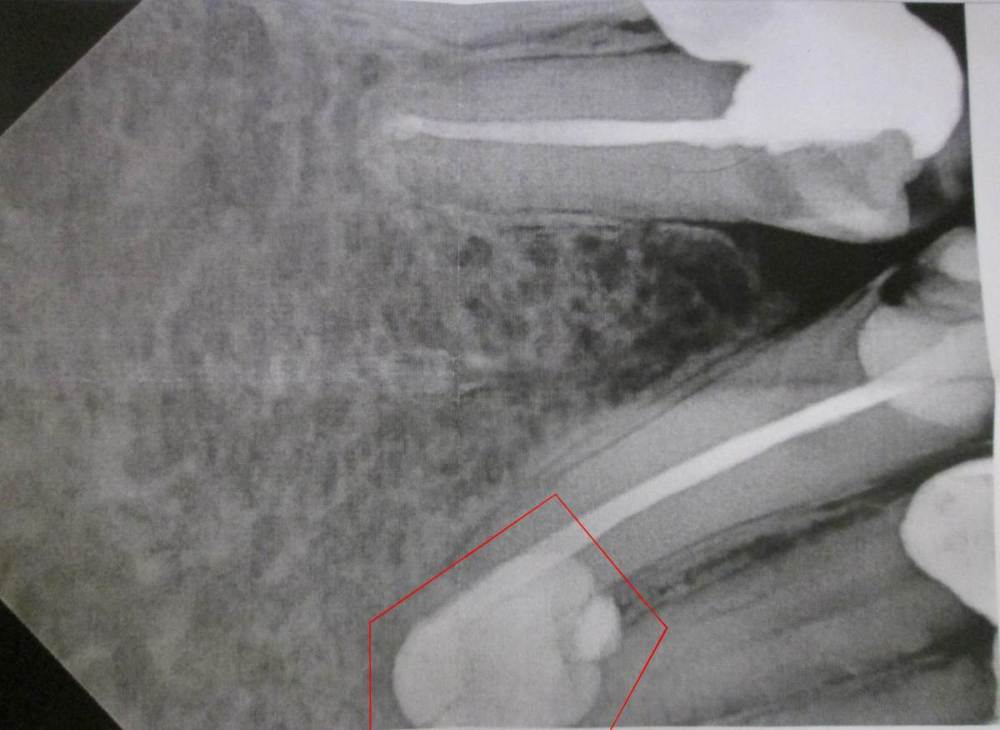

Hjolk332 Опубликовано 13 ноября, 2023 Поделиться Опубликовано 13 ноября, 2023 Добрый день. Я делал прицельный рентген снимок (прилагается) нижней челюсти, а именно клыка для постановки коронок. На снимке между клыком и боковым резцом было обнаружено образование (выделено). Рентгенелог сказал, что это может быть киста. Другой стоматолог сказал, что это не киста, так как образование на снимке белого цвета. На месте прощупывается уплотнение, при нажатии болезненное. Полгода назад в этом месте была сильная боль около недели, которая потом прошла. Боль списал на воспаление тройничного нерва. Если это киста и нечто типа этого можно ли ее удалить через десну, а не только через зуб. Спасибо Ссылка на комментарий

red_butler Опубликовано 13 ноября, 2023 Поделиться Опубликовано 13 ноября, 2023 Здравствуйте. По этому снимку не совсем понятно что это. Или пломбировочный материал, или "зачаток зуба", для уточнения сделайте компьютерную томографию . Ссылка на комментарий